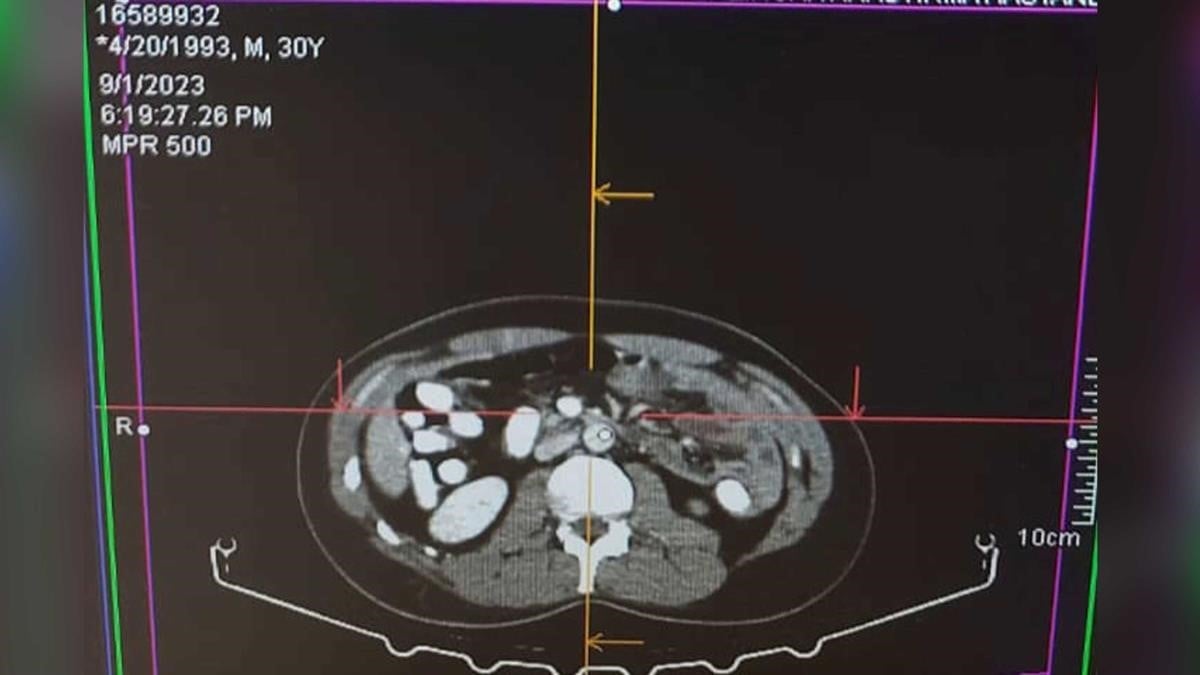

İl Emniyet Müdürlüğü Narkotik Suçlarla Mücadele Şube Müdürlüğü ile Kaçakçılık ve Organize Suçlarla Mücadele Şube Müdürlüğü ve İstihbarat Şube Müdürlüğü ekiplerince yapılan ortak çalışmada; Uygulama noktasında durdurulan, yolcu otobüsünde yolcu olarak bulunan A.A isimli şahsa alınan iç beden muayenesi kararına istinaden hekim gözetiminde çekilen “tomografi” neticesinde mide ve bağırsak kısmında uyuşturucu madde olabileceği değerlendirilen yabancı maddeler tespit edildi.

Şahıs Mengücek Gazi Eğitim ve Araştırma Hastanesinde müşahede altına alınarak midesinden 70 adet kapsül halinde daralı ağırlığı ise 499,23 gr Afyon sakızı maddesi ele geçirildi.